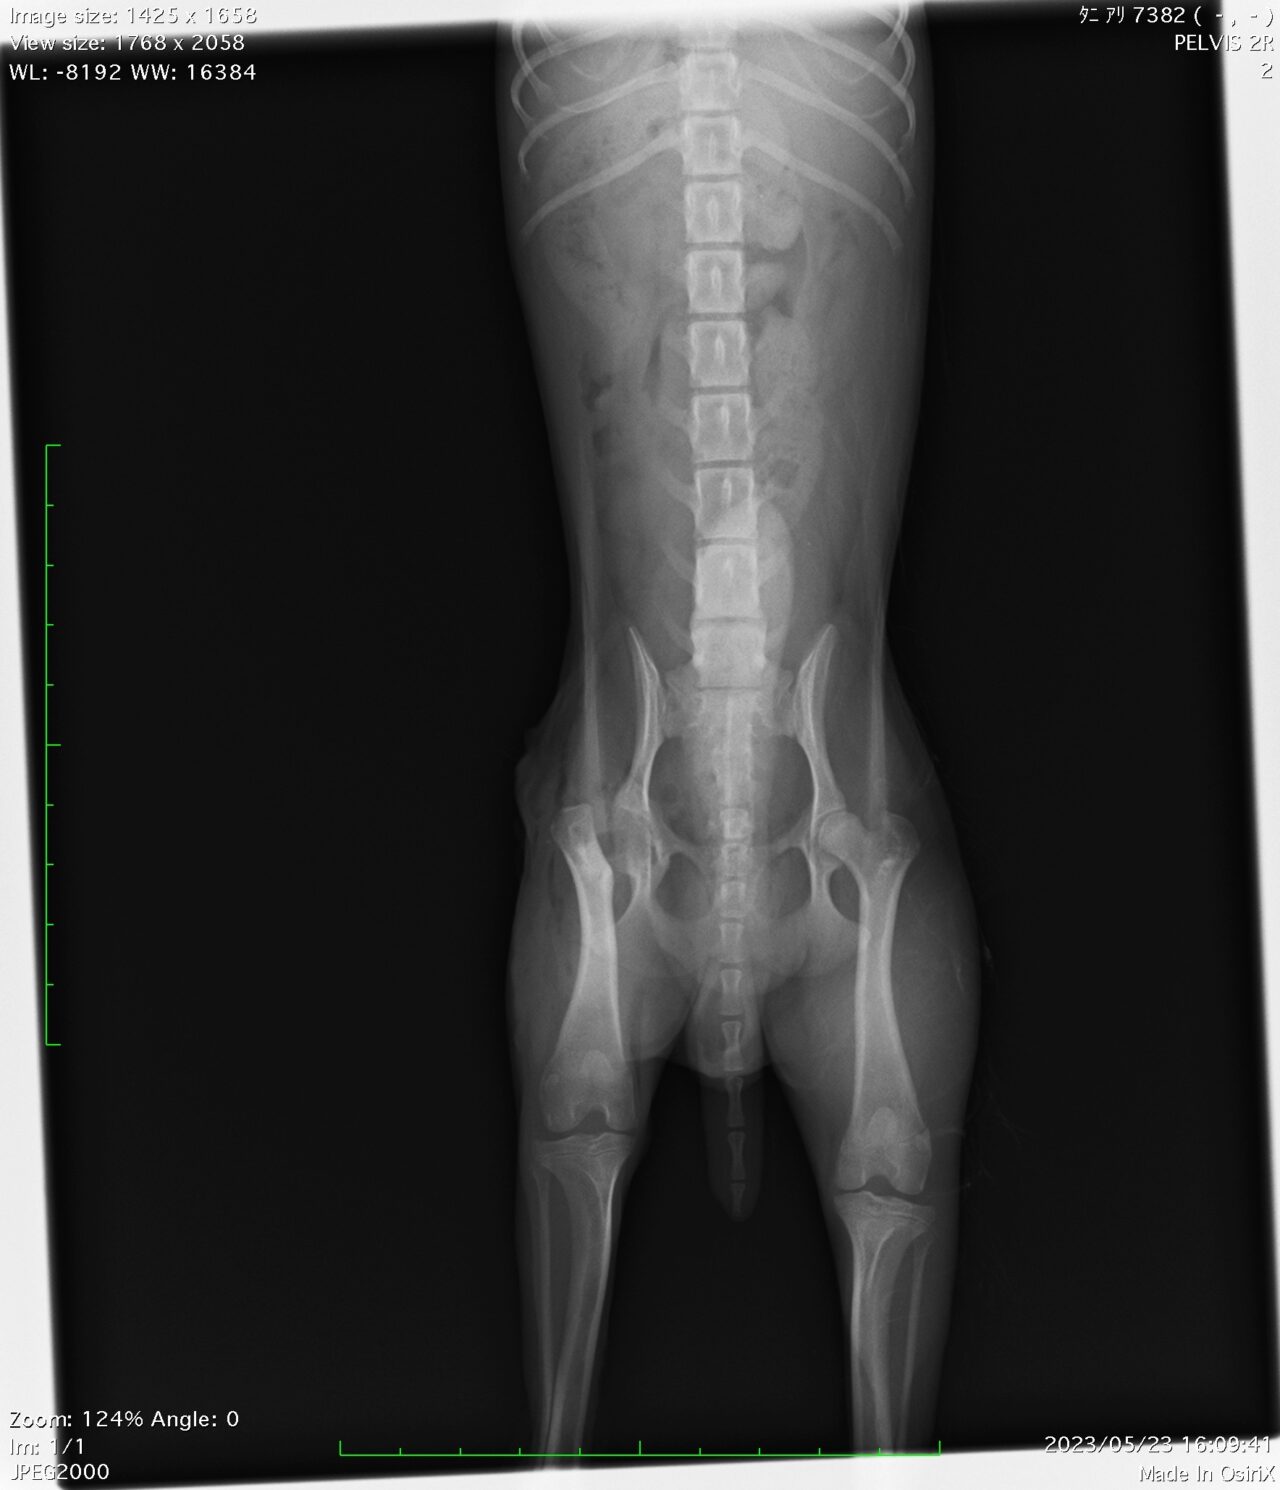

今回は若いわんちゃんに多い大腿骨頭壊死症、いわゆるレッグペルテス病についてです。

この病気は若い小型犬さん、特にプードルやヨーキー、チワワなどでよくみられる先天的な疾患です。

骨の一部が無菌性に融解していまい、進行性の病変でスカスカになっていき、場合によっては骨折を生じることもあります。

症状としては軽度の歩様異常から始まり、進行してくると太ももの筋肉が落ちてしまうことで症状が顕著になってきます。

そして診断にはレントゲンが必要になります。

この子の場合は、右後肢の青丸で囲まれた大腿骨の一部がモロモロになっているのがわかります。

さらに、反対の後肢と比べて筋肉量が顕著に落ちてしまっているのがよくわかります。

実際には、レントゲンではわかりにくい症例もあり、当院では怪しい場合はCT検査で確定診断をつけにいくこともあります。